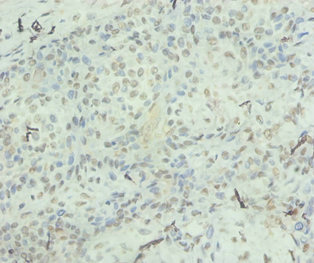

Immunohistochemistry of paraffin-embedded human breast cancer using CSB-PA08327A0Rb at dilution of 1:100